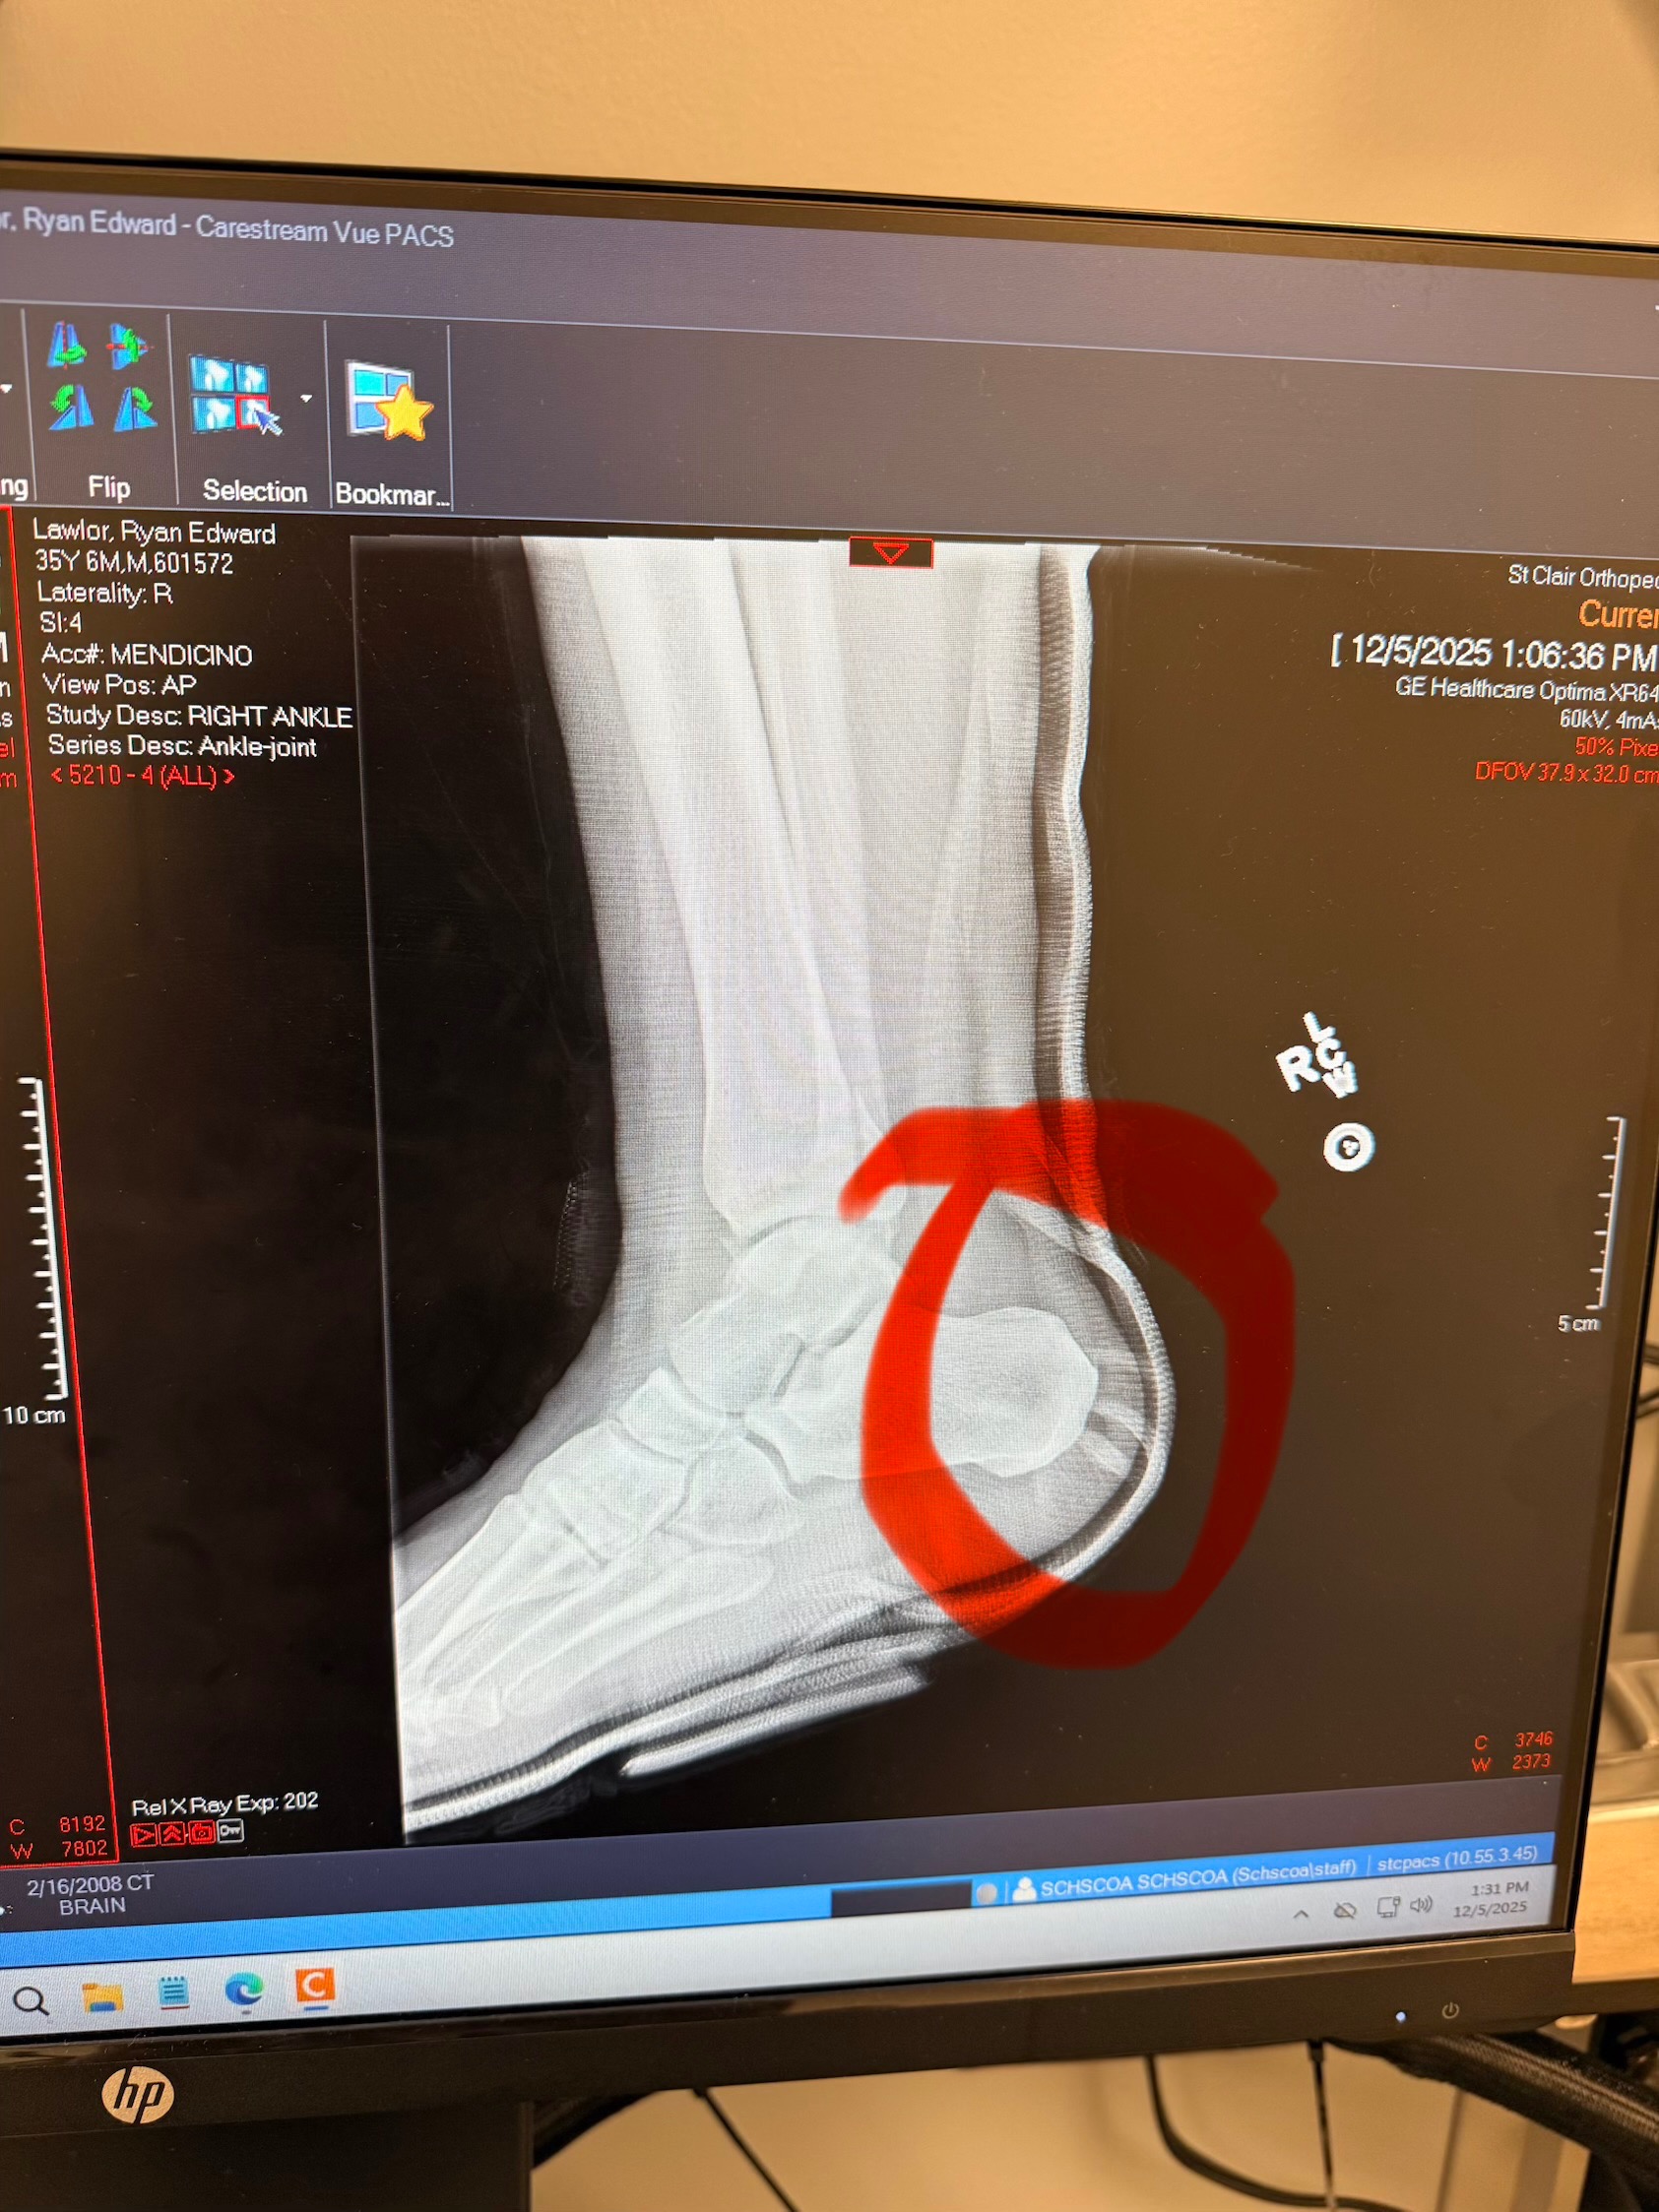

Hi, I am writing on behalf of my son. He fell and broke his tibula, fibula and tore all the tendons in his ankle. He does have health insurance to pay for this, but will be off for at least 12 weeks and does not have any short-term disability. He needs help paying his rent and monthly bills as he is a server at a downtown restaurant. He has a 3-year-old son that he also cares for. Any help that you would be able to give would be so greatly appreciated. No matter how small the donation is every bit helps.